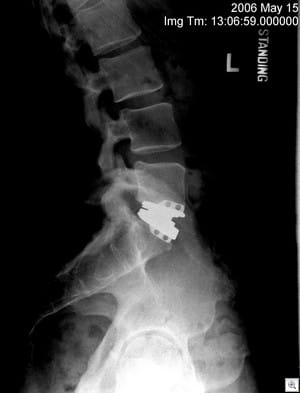

In early 2006, after years of progressively worsening chronic pain due to a damaged lower back, I had surgery to remove the lumbar disc at the L5/S1 level of my lower spine. The failed disc was replaced with a new device – a three-piece metal joint called the Kineflex Lumbar Disc – which was under FDA study as an alternative to fusing the two bones together.

The artificial joint, which is made of a strong, durable cobalt chromium alloy (and should last longer than I do, or so I am told), maintains the natural movement of the back and that joint, whereas a fusion locks the joint up and grows the two bones together into one. In theory, the result is better overall, since a fusion transfers the load and movement (and the resulting wear and tear) to the adjacent joints. The artificial disc mimics the body's normal range of motion.

It was a serious, heavy duty procedure, known as an anterior approach (good description here), which involved cutting me open below my belly button and moving all my guts and stuff out of the way in order to get access to my spine from the front. Then they cut the ligaments along the joint, removed the badly damaged disc (a shock-absorbing-like structure between the vertebrae) and replaced it with the artificial disc. That process consisted of cutting slots in the bones to anchor the device, spreading the joint out, and sliding the new artificial joint in place. Then they sewed me back up.